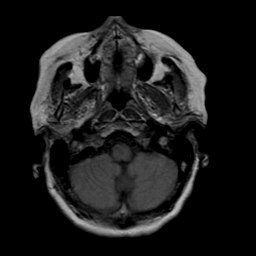

Stroke: proton density-weighted MR #2 -- Slice #2

[Home][Help][Clinical] Slice 2